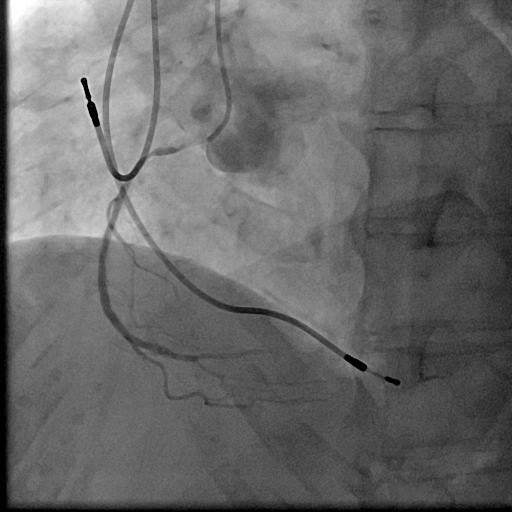

We used 7Fr JR3.5SH guiding and SION blue ES wire. Wire was easily crossed, and IVUS showed in-stent restenosis with neointimal hyperplasia and underexpanded stent. Long inflation technique using cutting balloon was performed, and Biolimus-A9 coated stent was deployed for in-stent lesion. Post dilation using NC balloon was performed, and procedure was completed. 4 months and 1year and 9 months after the procedure, follow up CAG with coronary angioscopy was performed.

1 year and 2 months after the initial procedure using underexpanded stent for eccentric calcified plaque placed at RCA ostium, in-stent restenosis was occurred. PCI was performed with drug-coated balloon and another 8 months later, re-restenosis was occurred. PCI was performed again with Biolimus-A9 coated stent deployed for in-stent lesion. 4 months, and 1 year and 9 months after the stent implantation, CAG was performed with evaluating coronary angioscopy. At the 4 months later, there was no restenosis and we confirmed beginning of neointima coverage for stent strut. At the 1 year and 9 months later, there was also no restenosis, and we confirmed enough and optimal neointimal coverage as vessel healing after stent implantation. Biolimus-A9 coated stent has early drug release system and polymer-free characteristics. The characteristics of the stent may have contributed to get the early smooth and optimal neointimal coverage, and the prevention of malignant cycle of RCA ostium in-stent restenosis.